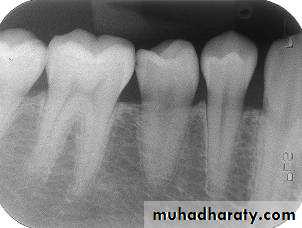

Advantages of the Paralleling Technique

1. Geometrically accurate images are produced with little magnification.2. The shadow of the zygomatic bone appears above the apices of the molar teeth.

3. The periodontal bone levels are well represented.

4. The periapical tissues are accurately shown with minimal foreshortening or elongation.

5. The crowns of the teeth are well shown enabling the detection of proximal caries.

6. The horizontal and vertical angulations of the X-ray tube head are automatically determined by the positioning devices if placed correctly.

7. The X-ray beam is aimed accurately at the centre of the film — all areas of the film are irradiated and there is no cone cutting.

8. Reproducible radiographs are possible at different visits and with different operators.

9. The relative positions of the film packet, teeth and X-ray beam are always maintained, irrespective of the position of the patient’s head. This is useful for some patients with disabilities.